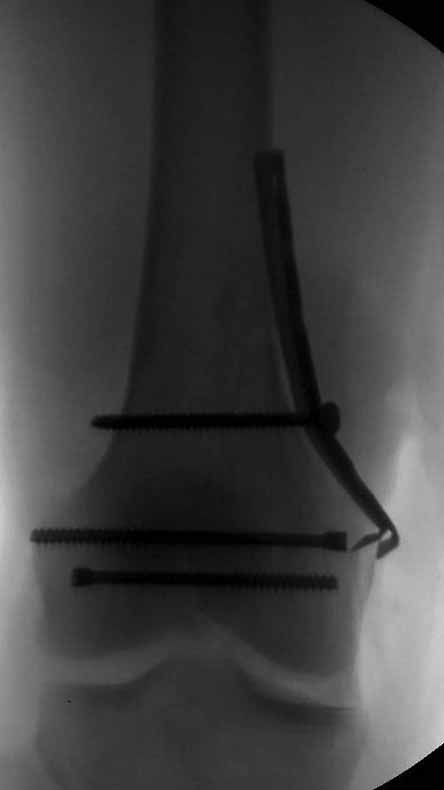

У больных как в этом случае, с вовлечением двух мыщелков правильно, что сделали вытяжение до операции. Здесь имеется флексионный компонент на другой стороне, и я бы рекомендовал операцию делать из двух доступов. Сперва фиксировать медиальную колонну custom made пластиной, обычно 1/3 тубулярной пластиной в 4.5 мм, потому что пока производители опаздывают с медиальной пластиной.

Пластину надо устанавливать на апексе перелома, иначе фрагмент начнет сползать. А на второй стороне, если имеется большой одиночный фрагмент тогда проблем не бывает, и их можно собрать компрессирующими винтами. Проблема наступает тогда когда многофрагментраность на латеральной стороне, где надо применить комбинированный метод, иногда несколькими пластинами. Или сменой позиции установки пластины, чтобы максимально прикрыть перелом и создать боковую поддержку.

Здесь пример медиальной пластины и латеральный комбинированный метод (у второго больного старый перелом тибиал плато, леченный где то и когда то)